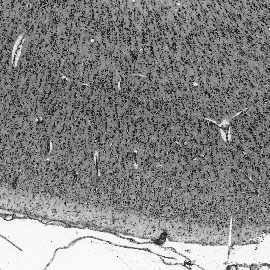

Cytoarchitectonic maps provide microstructural reference parcellations of the brain, describing its organization in terms of the spatial arrangement of neuronal cell bodies as measured from histological tissue sections. Recent work provided the first automatic segmentations of cytoarchitectonic areas in the visual system using Convolutional Neural Networks. We aim to extend this approach to become applicable to a wider range of brain areas, envisioning a solution for mapping the complete human brain. Inspired by recent success in image classification, we propose a contrastive learning objective for encoding microscopic image patches into robust microstructural features, which are efficient for cytoarchitectonic area classification. We show that a model pre-trained using this learning task outperforms a model trained from scratch, as well as a model pre-trained on a recently proposed auxiliary task. We perform cluster analysis in the feature space to show that the learned representations form anatomically meaningful groups.